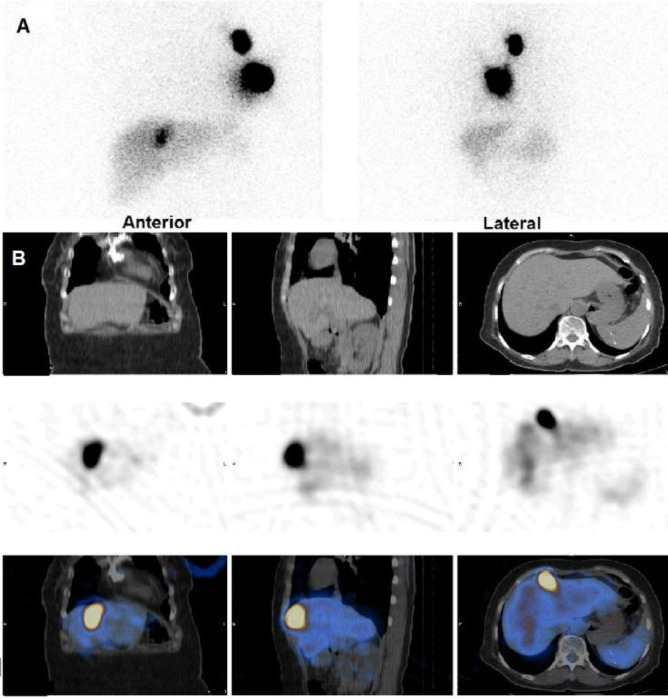

Breast cancer lymphoscintigraphy is a crucial tool in pre-operative assessment, typically revealing sentinel lymph node drainage patterns within axillary and extra-axillary regions. However, rare cases challenge conventional understanding. We report a 67-year-old woman with breast cancer, where lymphoscintigraphy revealed focal uptake within the falciform ligament of the liver, an exceedingly rare phenomenon. Clinical examination and imaging showed no axillary lymph node involvement. Lymphoscintigraphy and subsequent Single-photon emission computed tomography (SPECT)/computed tomography (CT) uncovered two axillary lymph nodes and an atypical focal uptake in the falciform ligament. Histopathology revealed no metastasis in sentinel nodes. The conventional understanding of breast lymphatic drainage primarily involves axillary and extra-axillary pathways, with the falciform ligament rarely implicated. This case suggests a unique lymphatic pathway connecting the breast and liver, possibly influencing metastasis. Factors such as lymphatic obstruction and valvular incompetency may contribute. This case highlights the importance of comprehensive lymphatic mapping in breast cancer evaluation and underscores the need for further research into atypical lymphatic pathways.